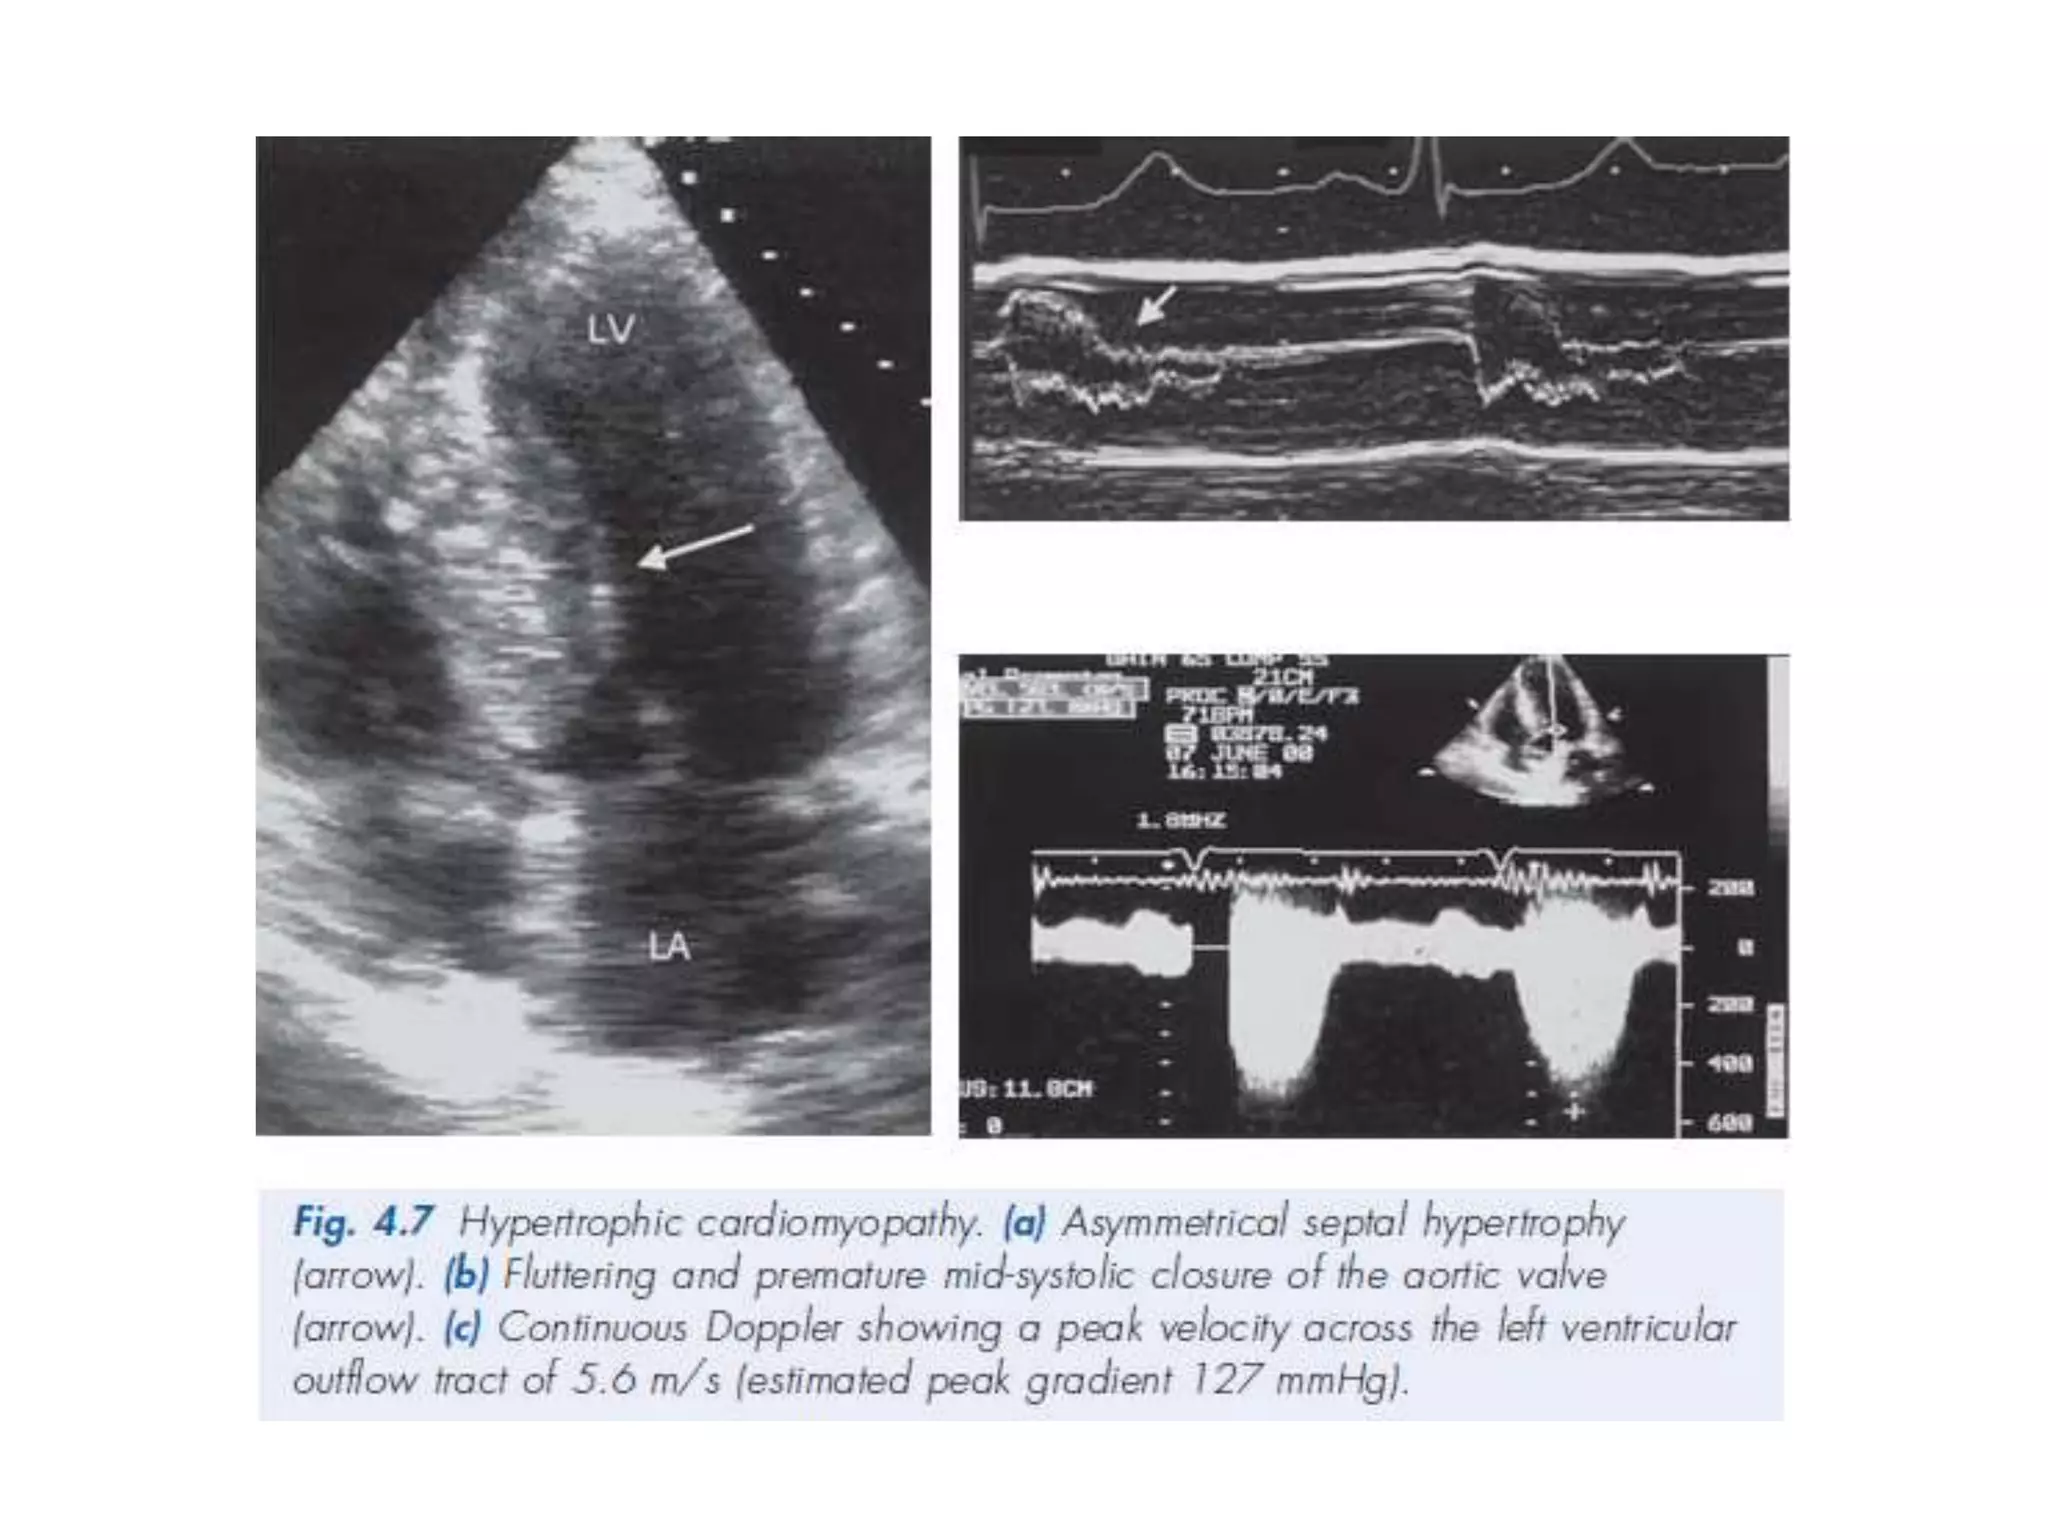

HCM

• 58.